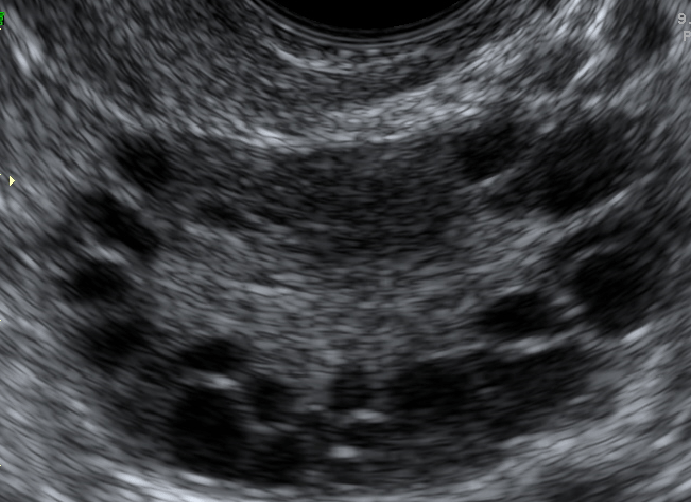

Avaliação Ultrassonográfica

Para que ultrassonografia seja compatível com ovários policísticos (OP) é necessário ter pelo menos um dos seguintes itens em pelo menos um dos ovários15:

- Presença de 12 ou mais folículos em cada ovário com medida entre 2-9 mm de diâmetro; OU

- Aumento de volume ovariano (> 10cm³).

Figura 3. Aspecto ultrassonográfico dos ovários policísticos, identificando 12 ou mais folículos de 2-9 mm de diâmetro.

Quando há evidência de dominância folicular (folículo com diâmetro médio maior que 10 mm) ou de ovulação recente (corpo lúteo), a ultrassonografia deverá ser repetida no próximo ciclo e a conclusão diagnóstica, postergada. É importante salientar que a distribuição periférica e o aumento da ecogenicidade ovariana podem ser omitidos, já que, sem as características citadas anteriormente, não servem para o diagnóstico de OP15.

Além disso, essa definição não se aplica em mulheres em uso de anticoncepcionais orais. Mulheres que estejam menstruando regularmente deverão ser submetidas à avaliação US na fase folicular precoce (3-5º dia do ciclo). Mulheres com oligo/amenorréia poderão ser submetidas à US ao acaso ou do 3-5º do fluxo menstrual após sangramento induzido por progestagênios15.